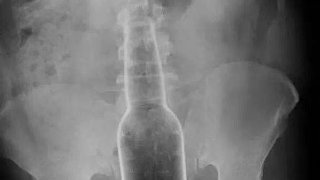

หลุดมือ? หนุ่มเอาขวดแก้วมาเกาก้น ขวดผลุบเข้าไปทะลุถึงไส้

โดย

โคนันเอง

(ตอบ 22, 6Y)